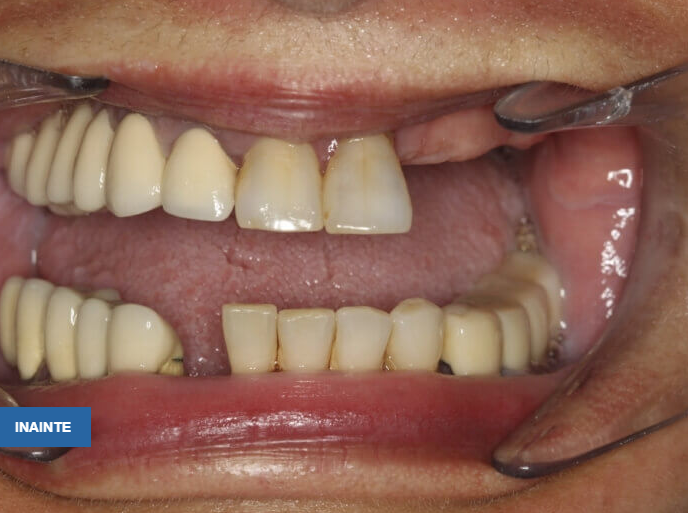

Pacienta în vârstă de 46 ani se prezintă în clinică având edentație uniterminală bimaxilară (maxilar 1 modificare, mandibulă 4 modificari) cu parodontopatie marginală cronică profundă, dinții prezentând mobilitate grad 3, o proteză mobilă parțial acrilică incorect adaptată campului edentat cauzând inflamația mucoaselor pe care se sprijinea, restaurări protetice fixe metalo-ceramice incorect adaptate, unele fixate provizoriu pe bonturi fracturate, reacții periapicale.